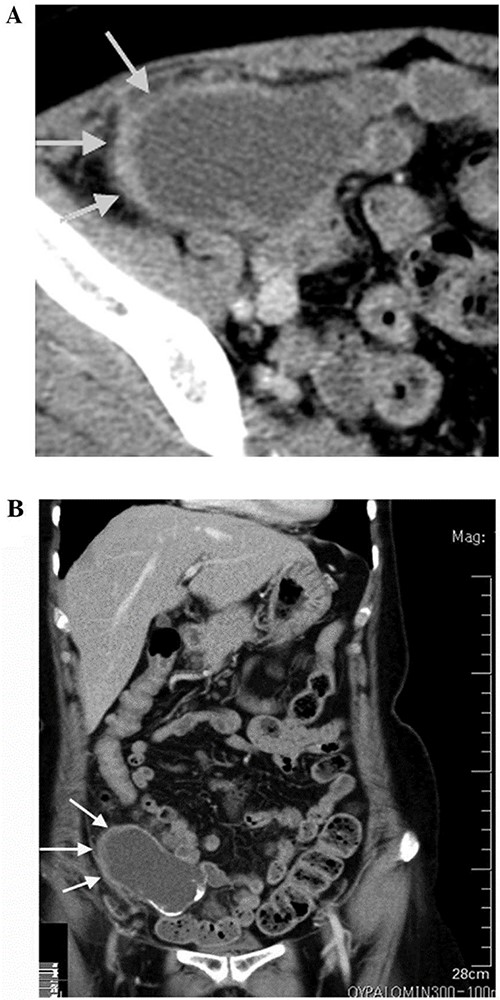

Computed tomography (CT) scan was performed after perfusion of a radiopaque substance through the vein in both arterial and venous phases. It exhibited a 14-cm lobulated cystic formation in the level of the right iliac vessels with an extension to the upper margin of the pelvis. The wall of the cyst was thick and calcinated (Fig. 1).

CT scan showing lobulated cystic formation in the right iliac vessels level with an extension to the upper margin of the pelvis. This finding is suspicious, so a decison was made for excision of the tumor and to be sent to pathology department to confirm the diagnosis.

Both echography and CT scan displayed normal findings for other inner organs within the abdominal cavity and confirmed the absence of free fluid.

Often, this malignancy is misdiagnosed as acute appendicitis, retroperitoneal tumors in the right iliac fossa or an adnexal mass. Imaging tools used for diagnosis are ultrasound and CT. CT findings include cystic dilation within the appendiceal lumen with wall calcifications and irregular appendiceal wall thickening as demonstrated in our case. Grossly, specimens include hyalinization and fibrosis of the appendiceal wall with a grossly swollen appendix secondary to mucinous accumulation [4].